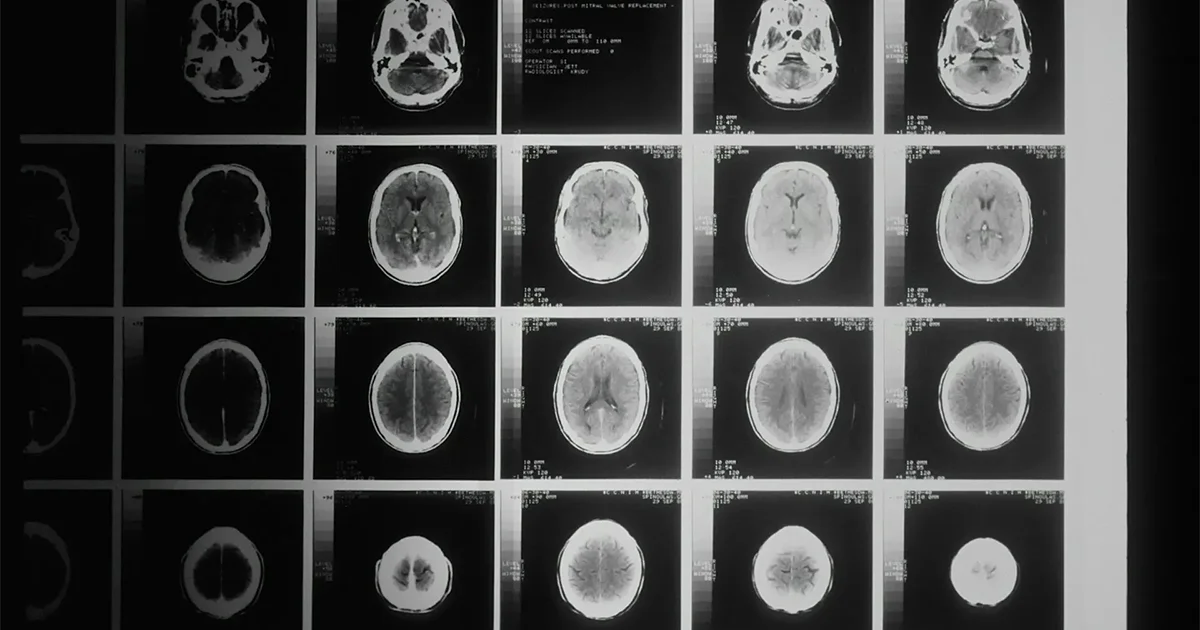

A traumatic brain injury occurs when an external force—such as a car crash, fall, or sports accident—disrupts the normal function of the brain. The Centers for Disease Control and Prevention (CDC) classifies TBIs as mild, moderate, or severe. Concussions are the most common form of mild TBI, yet they can still have serious, lasting consequences.

Unlike visible injuries, brain injuries are often invisible. CT scans or MRIs may appear normal, even when victims experience significant cognitive or emotional symptoms. This can make proving the extent of the injury in court particularly challenging.